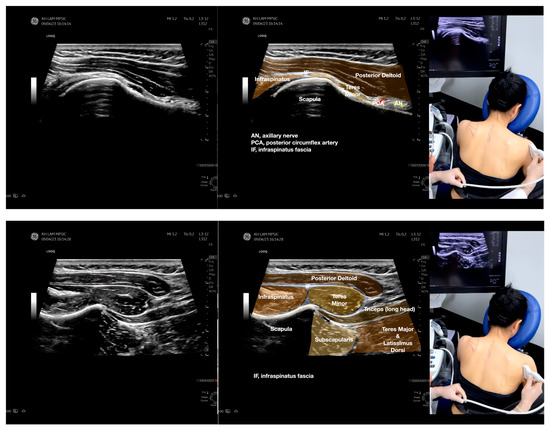

Figure 4.

Sonoanatomy of the medial edge of the scapula, its related muscles, and the infraspinatus fascia. The step-by-step scanning techniques of these structures illustrated in this figure have been shown in Video S8. Available online: https://www.dropbox.com/s/iaej3rxhl83kqt4/Figure%204.docx?dl=0 (accessed on 1 January 2023).